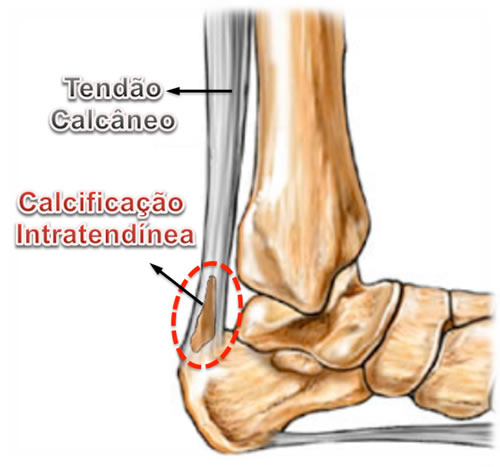

- Calcificação Intratendínea (Esporão do Tendão de Aquiles)

A calcificação intratendinea, popularmente chamada de esporão do tendão de Aquiles, forma-se por uma alteração celular degenerativa das fibras do tendão. Isto ocorre pela alternância, durante um longo período de tempo, entre os processos de inflamação, micro ruptura e reparo local. Portanto, a constante tentativa de cicatrização de uma lesão crônica do tendão leva à sua degeneração e calcificação local de suas fibras.

A tendinite insercional ocorre junto ao osso do calcanhar e muitas vezes está relacionada às deformidades da proeminência superior e posterior do calcâneo (Deformidade de Haglund) ou a formação de calcificação interna do tendão (esporão).